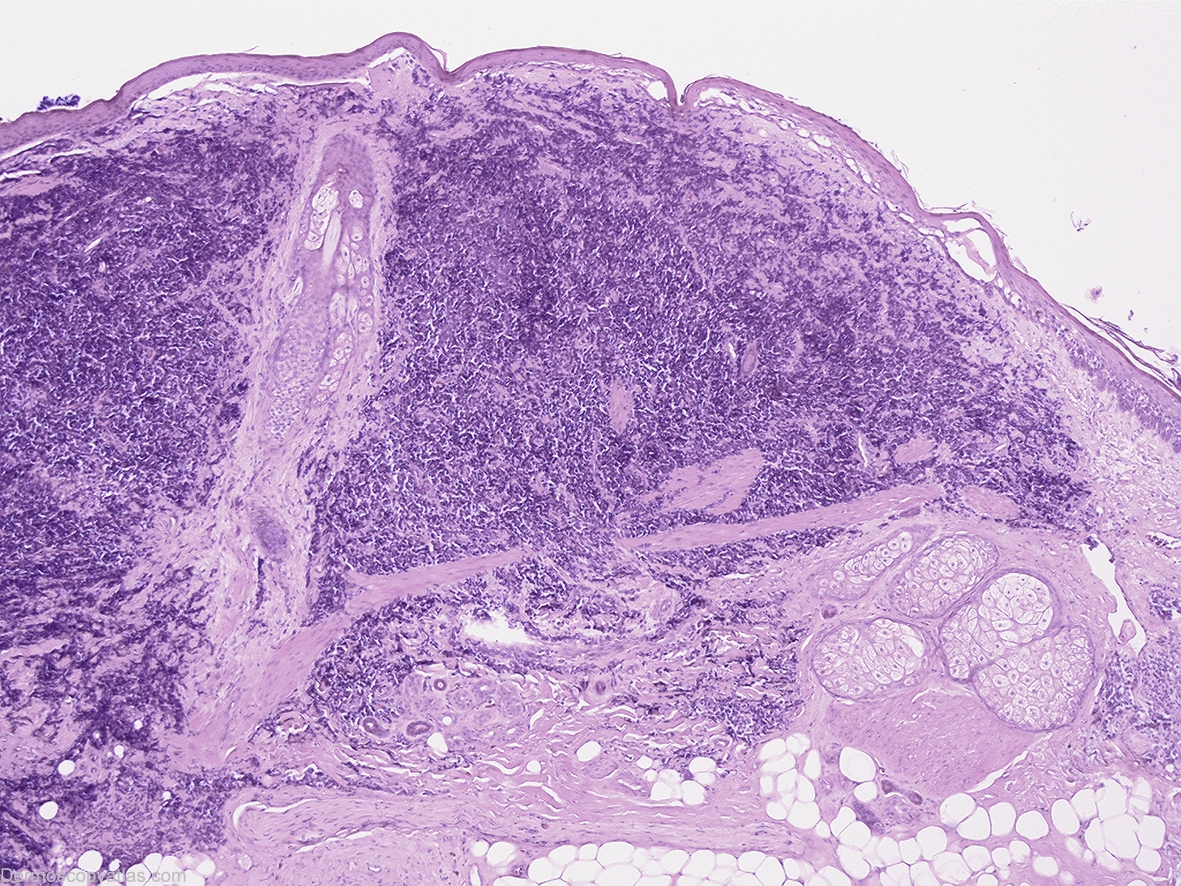

Diagnosis: Merkel cell carcinoma

History: This 83 year old gentleman presented for a routine skin check and this lesion was discovered. Prior to biopsy this lesion was lasered without biopsy by another practitioner but subsequent wide excision of the area discovered a residual dermal based Merkel cell carcinoma at the site where this lesion had been.